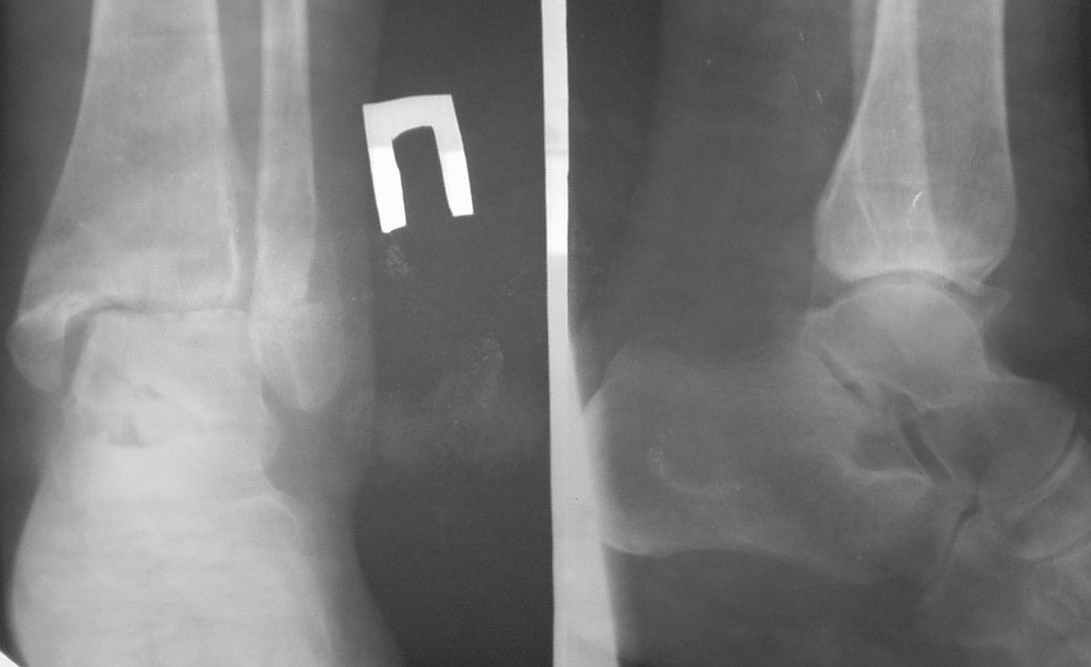

На консультацию пришла больная 39 лет, перелом лодыжек 8 месяцев назад. Лечилась консервативно в одном из стационаров области.Сейчас беспокоят постоянный болевой синдром и отек, затрудняющий ношение стандартной обуви. На КТ - межберцовый синдесмоз 4,5 мм (на здоровой ноге - 2,0 мм). Деформирующие краевые костные разрастания по внутренней замыкательной пластине мало-, большеберцовой и таранной костей. Какие будут соображения по дальнейшей тактике: 1. надо-ли оперировать?2. если "да", то что делать?

У больной неправильно сросшщийся перелом внутренней лодыжки (передний

"клюв" порядка 5 мм).

О наружной лодыжке (угол, длина) - даже не упоминаю.

артродез сделать никогда не поздно. Я бы начал с реконструкции: ревизия зоны синдесмоза, перелома в/лодыжки ( скорее всего там ложный сустав) и внутренней части сустава. Затем стяжка и остеосинтез в/лодыжки.